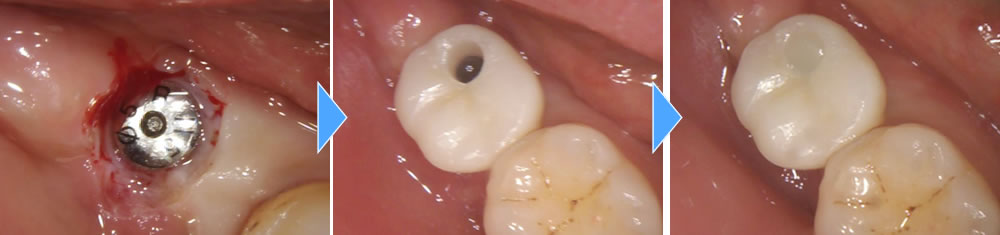

上部構造の装着・治療完了

顎骨とインプラントの結合を確認後、上部構造を作製・装着して治療完了となりました。術後は痛みが出る前と同じように奥歯でしっかりと噛むことができるようになり、大変満足していただいております。